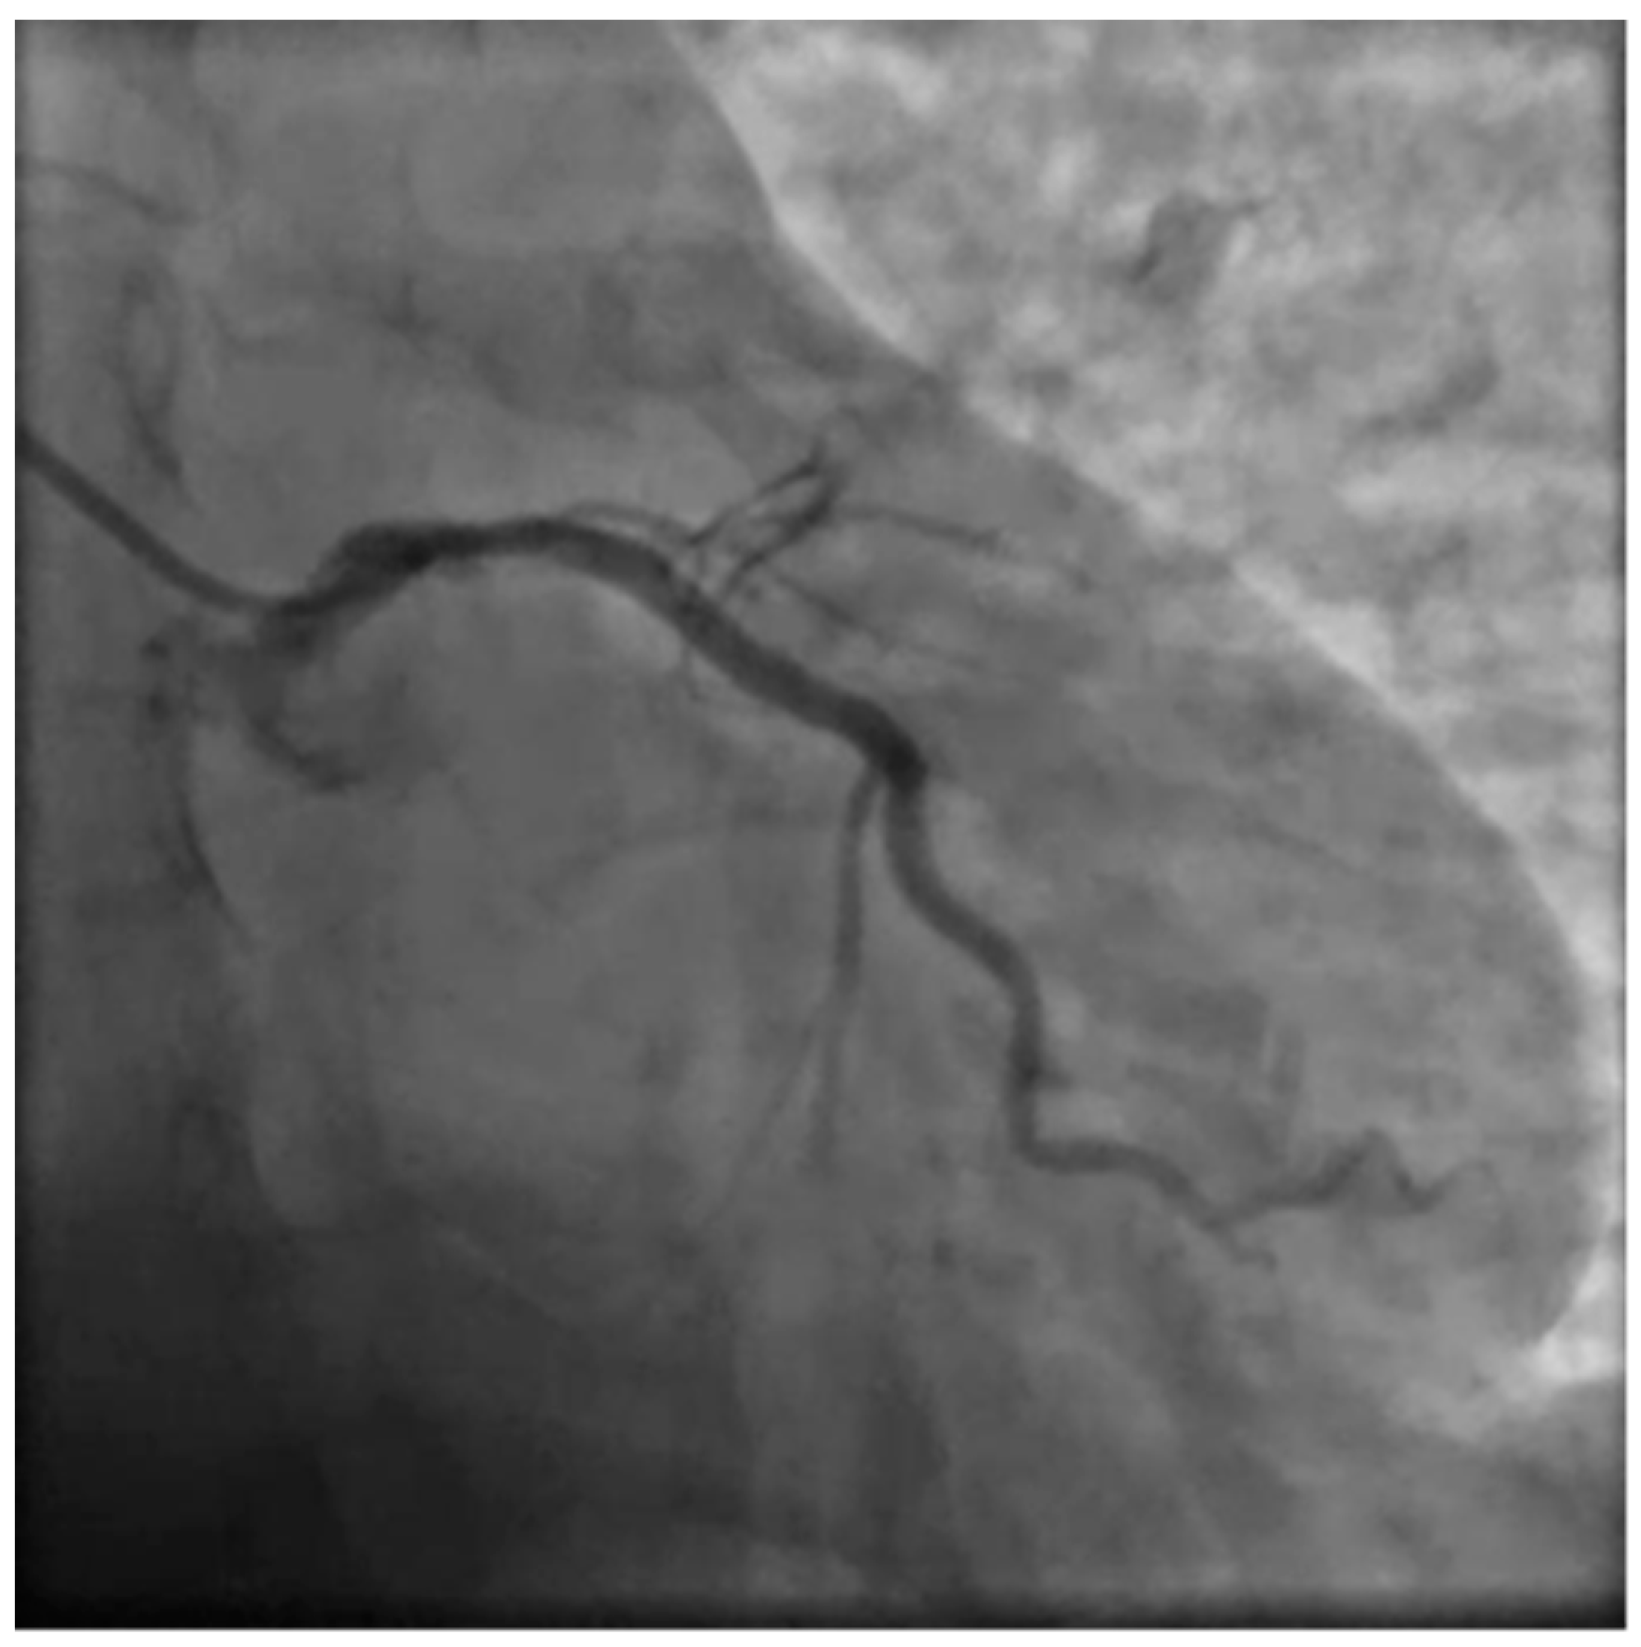

Due to the unusual setting involving a 36 weeks pregnant woman several other specialists were involved in the care process setting up an emergency pregnancy heart team involving cardiologists, gynecologists, anesthesiologists, pediatricians and the radiology specialist. Due to the unstable and acute condition of the woman a decision was quickly made to proceed with an emergency coronary angiography and PCI. A rapid response gynecology team followed the procedure ready to intervene promptly in case of maternal deterioration with unresponsive cardiac arrest. A 6F left radial access was obtained, aiming to be as coaxial as possible, and the left coronary artery angiogram was obtained with a standard 6F JL 3.5 catheter showing LM dissection involving the ostial LAD which showed complete occlusion with TIMI 0 flow.

Figure 4. Basal PA caudal projection.